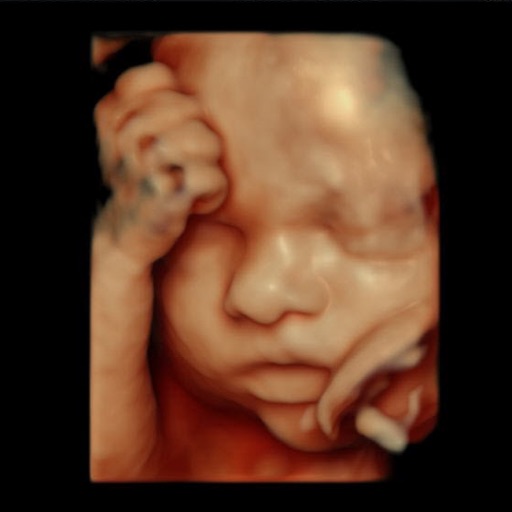

3D ultrasound scan of baby before AI processing

4D ultrasound image uploaded to baby face reveal AI

Simply upload a clear ultrasound image of your baby's face. Our system works best with 3D or 4D ultrasound images.

3D and 4D ultrasound images produce the best results because they show facial features more clearly. Standard 2D ultrasounds can also work, but results vary depending on image quality and baby position. The clearer the facial features are visible, the better the AI prediction.

The best results come from ultrasounds taken between weeks 24–32 of pregnancy, when the baby's facial features are developed but there's still enough amniotic fluid for a clear scan. 3D/4D ultrasounds from this period typically give the most accurate and beautiful baby face predictions.